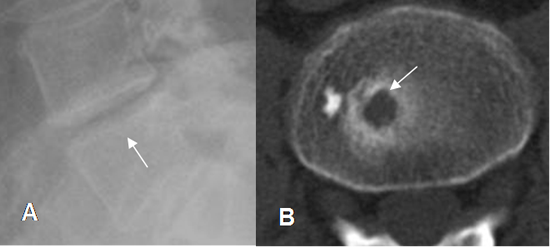

Fig 114. Nódulo de smorl.

A: Rx lateral. Irregularidad en la placa terminal superior.

B: TAC axial. Defecto de bordes escleróticos en la placa terminal, que corresponde a nódulo de smorl.

En las diferentes modalidades se aprecia como una indentación en la placa terminal, de bordes escleróticos, asociados o no a espondilosis y otros cambios degenerativos vertebrales. (27). (Fig 114 y 115).